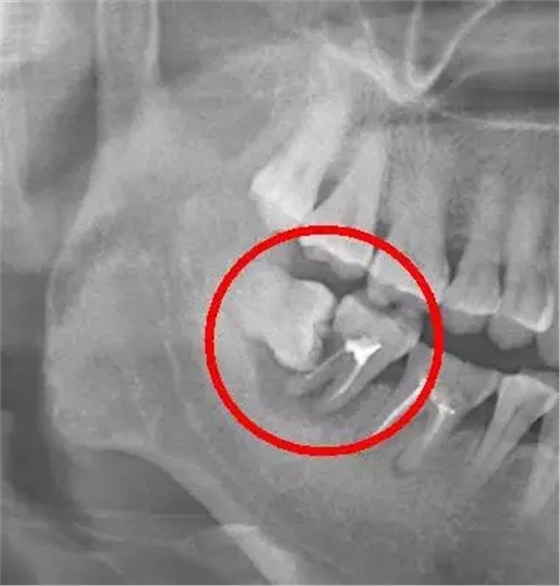

口說(shuō)無(wú)憑,上病例。來(lái)看下面這例

這種情況就因?yàn)闆](méi)及時(shí)拔除智齒,最終的結(jié)果就是把鄰牙也拖下水,兩顆牙齒一起報(bào)銷(xiāo),旁邊的第二恒磨牙本來(lái)就容易因?yàn)榍鍧嵅粡氐x壞的好么,還要無(wú)端被拖著陪葬,真是生存不易。更慘的是,鄰牙拔除之后,還必需要裝上一顆種植牙補(bǔ)上(我會(huì)告訴你裝一顆種植牙花費(fèi)上萬(wàn)是很正常的么),得不償失?。。?/span> 下面這例又是一個(gè)悲傷的故事: 需要特別注意的是,鄰牙病變具有一定的隱蔽性,通常的情況是可能旁邊牙齒已經(jīng)被頂壞了,患者還沒(méi)有任何感覺(jué),這就需要拍一張口腔 X 光片才能進(jìn)行準(zhǔn)確的診斷。 智齒萌出位置不正,即使沒(méi)有頂壞鄰牙,也可能與鄰牙形成間隙,產(chǎn)生局部的“衛(wèi)生死角”,食物殘?jiān)图?xì)菌堆積在這些部位,我們?nèi)粘K⒀篮茈y清潔到,久而久之就容易引發(fā)齲齒 如果智齒的對(duì)面沒(méi)有對(duì)頜牙,有時(shí)就會(huì)發(fā)生智齒過(guò)度萌發(fā)伸長(zhǎng)的現(xiàn)象。智齒野蠻生長(zhǎng)、過(guò)度萌發(fā),甚至咬合時(shí)直接咬到對(duì)面牙齦上,造成咬合疼,進(jìn)而影響正常咬合。 看完上面,是不是有人在慶幸,自己智齒好像完全萌出,又長(zhǎng)得正沒(méi)有形成盲袋、也沒(méi)有頂?shù)礁粞?,是不是就不用拔了?/span> 來(lái)看下面這張,從X光片上看,兩顆智齒對(duì)頜萌出,位置看似也很正是吧。然而,拔下來(lái)之后是這樣的: 已經(jīng)爛掉了,有木有! “智齒不痛、長(zhǎng)得好像也還整齊,為什么醫(yī)生還要建議拔掉?” 上圖就是一個(gè)很典型的例子:看似好像長(zhǎng)得還不錯(cuò)的兩顆智齒,其實(shí)因?yàn)槲恢藐P(guān)系,不能很好的清潔、也缺乏正常的咬合關(guān)系,往往會(huì)有食物嵌塞、齲齒的發(fā)生,等到自己有癥狀的時(shí)候通常都很?chē)?yán)重了。 所以,最穩(wěn)妥的方式是:至少去拍一張牙片,讓牙醫(yī)用專(zhuān)業(yè)的眼光來(lái)幫你做出正確的判斷(也就一頓麥當(dāng)當(dāng)?shù)腻X(qián)好么 最后,說(shuō)下關(guān)于拔牙。很多人都對(duì)拔牙心存恐懼,所以拖著一直不敢去看牙醫(yī)。在他們的想象中,拔牙還是這樣的場(chǎng)面..... 或者這樣 NO!NO!NO! 別鬧了,已經(jīng)是21世紀(jì)了好么,我們?cè)缇筒挥缅N子敲敲打打,野蠻施工了。 現(xiàn)在我們都提倡微創(chuàng)拔牙,用拔牙挺,配合精準(zhǔn)的麻醉技術(shù),整個(gè)拔牙過(guò)程都可以保證是無(wú)痛的。 具體原理是:先進(jìn)行局部麻醉,然后用挺插入牙根和牙槽骨之間,牙挺的凹槽對(duì)著牙根面,左手保護(hù)鄰近牙齒,右手持牙挺,以牙槽骨為支點(diǎn),利用杠桿作用和轉(zhuǎn)動(dòng)力量,從近中或遠(yuǎn)中部位逐漸挺松牙齒,然后用拔牙鉗取下牙齒。